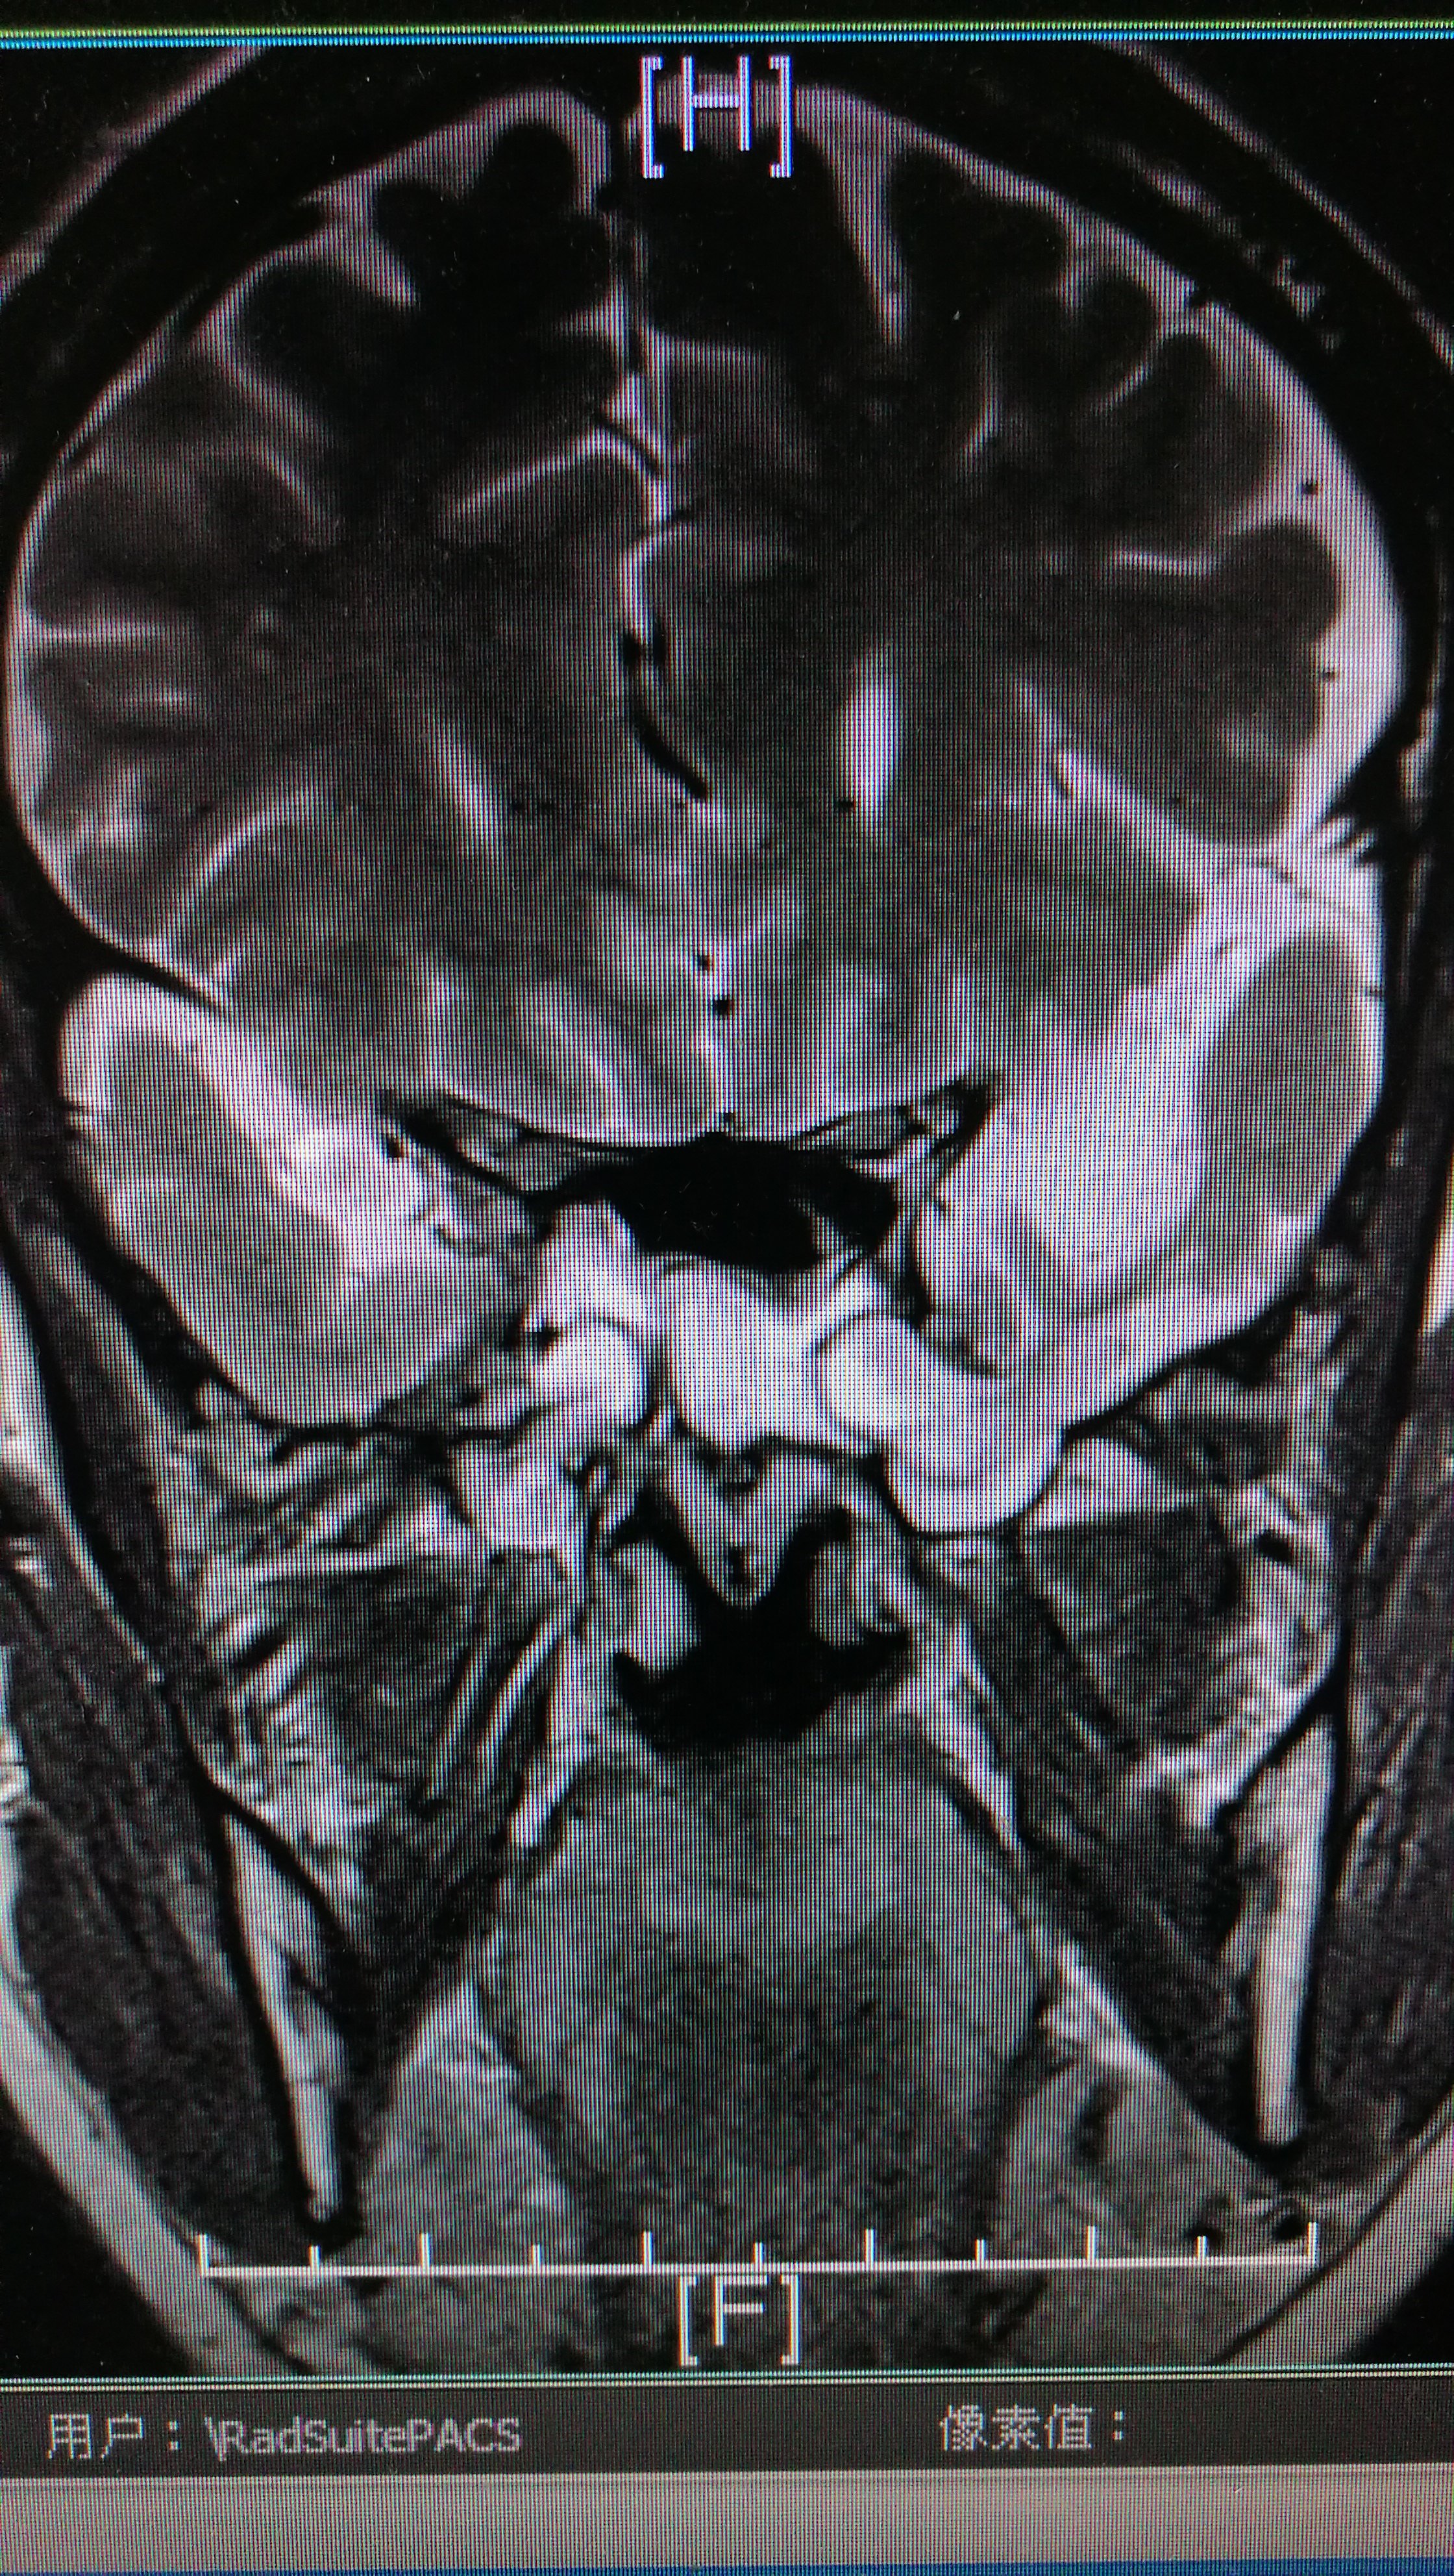

一例新生儿至幼儿期原发性脑膨出(颅裂畸形)治疗经验

图片尺寸828x960